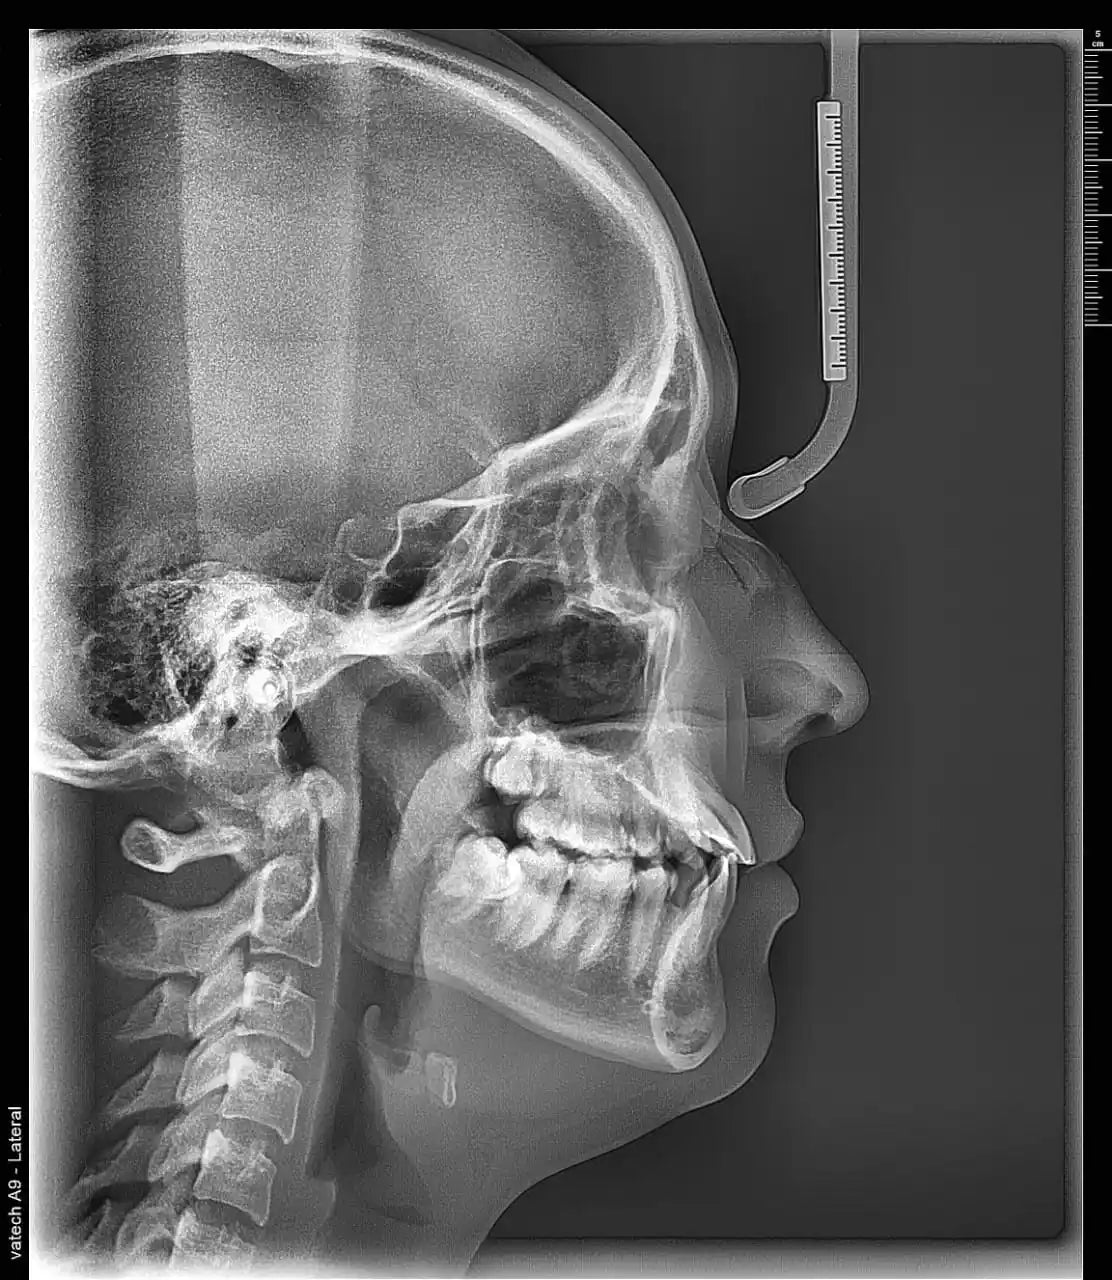

La radiografía lateral de cráneo

Es una técnica radiográfica extraoral mediante la cual se obtiene una vista lateral del cráneo y las estructuras óseas de la cara. La radiografía lateral de cráneo permite un estudio del crecimiento facial del paciente y una valoración de las estructuras maxilares, mandibulares y sus relaciones con la bases craneales. Muestra el trazado de las estructuras anatómicas y la localización de los puntos cefalométricos. La misma radiografía lateral de cráneo muestra los trazos para obtener las angulaciones resultantes del estudio cefalométrico